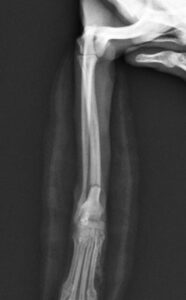

右前腕骨折のポメラニアンちゃんが来院されました。橈尺骨骨折は動物病院では一番よくある骨折です。ロッキングプレートであるTAITAN1.2で対応しました。治りも順調で元気に帰りました。よかったね。